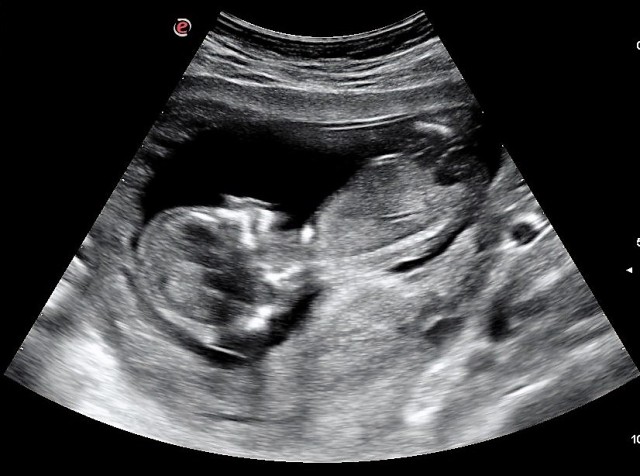

At First Choice, the services include: pregnancy testing, confirmation ultrasounds, pregnancy options education, STI testing and treatment, post-abortion support, individual/group parenting classes, Fathers First men's program and an on-site baby boutique.